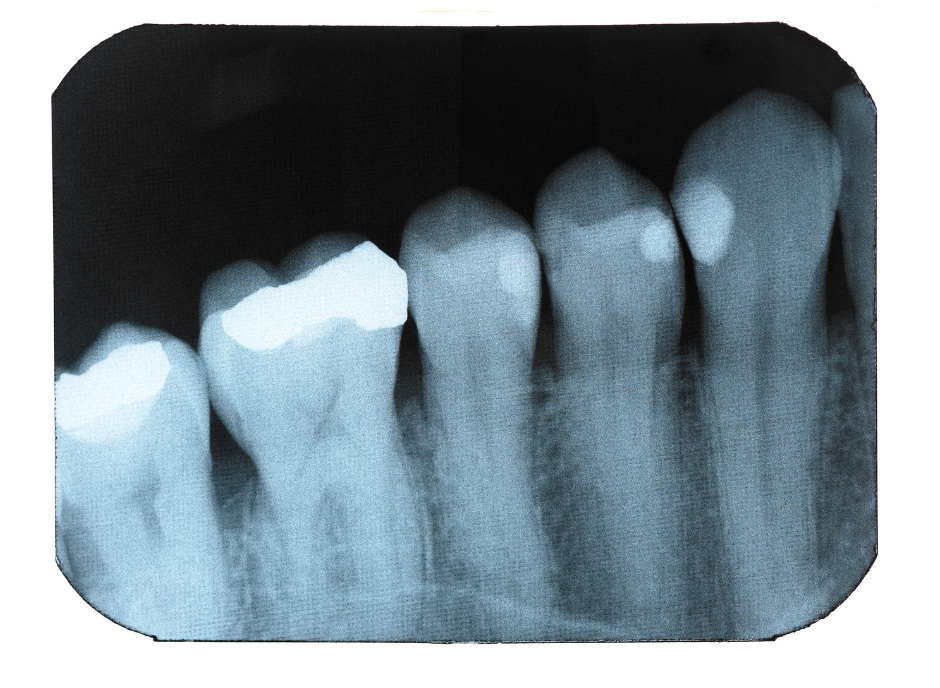

Rontgen Periapikal adalah jenis foto rontgen gigi yang digunakan untuk melihat seluruh struktur gigi secara detail, mulai dari mahkota gigi sampai ke akar dan tulang di sekitar ujung akar. Pemeriksaan ini sangat membantu dokter untuk mengetahui kondisi yang tidak terlihat hanya dari pemeriksaan biasa.

1. Mendeteksi infeksi di ujung akar gigi

Biasanya digunakan untuk melihat adanya abses atau peradangan pada akar gigi.

2. Membantu diagnosis sebelum perawatan saluran akar

Penting dalam perawatan seperti pada bidang Endodontics agar dokter bisa melihat panjang dan bentuk akar gigi.

3. Melihat kondisi tulang penyangga gigi

Berguna untuk mengevaluasi kesehatan tulang pada pasien dengan masalah gusi atau Periodontitis.

4. Mendeteksi gigi retak atau patah di bagian akar

5. Memeriksa keberhasilan perawatan gigi sebelumnya

Misalnya setelah tambal saraf atau operasi gigi.